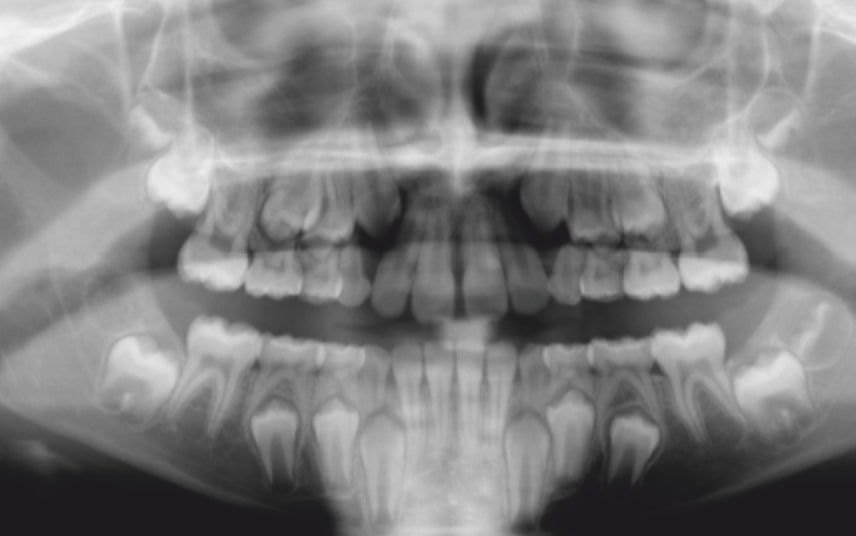

Malocclusion A6 Correction of Mandibular Retrusion in Growth phase patient | Skeletal Class II | Class II Division 1 malocclusion | Deep bite | Mixed dentition

Initial Photos and datas

Clinical examination and diagnosis

SKELETAL PATERN: Class 2

DENTAL:

• Molar and Canine class 2 on the right side – Molar and Canine clss 1 on the left side

• Upper diastema (11-21)

• Increased Overjet

• DeepBite

• Reduced Transversal Diameters

• Deviated Lower Midline 2 mm to the Right